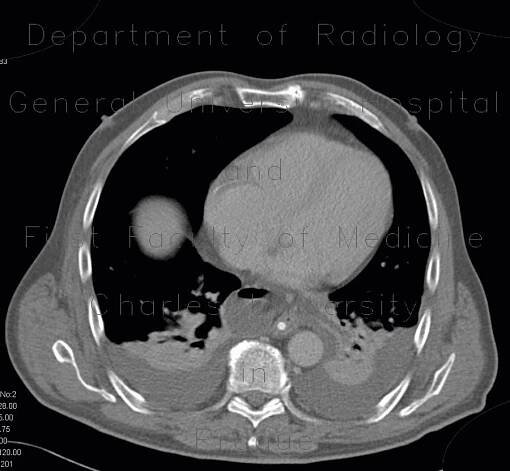

Computed tomography findings show a massive pneumoperitoneum

Pneumoperitoneum, mimic of epiphrenic diverticulum